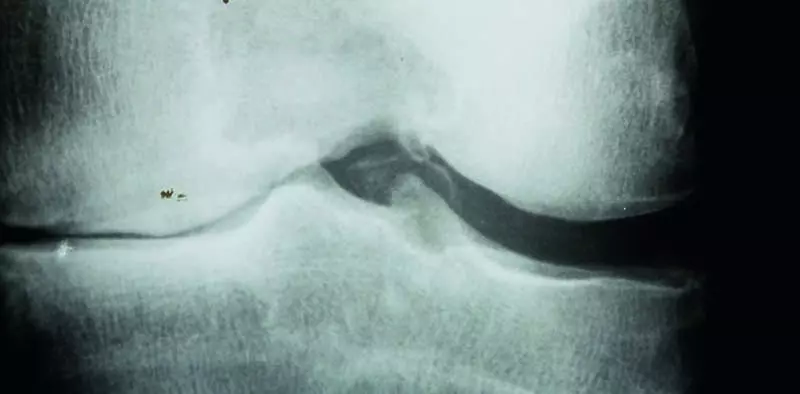

Staw kolanowy jest największym stawem ustroju ludzkiego. Łączy udo z golenią, przy czym ze strony podudzia tylko kość piszczelowa uczestniczy w tym połączeniu. Staw kolanowy jest stawem złożonym, gdyż biorą w nim udział trzy kości:

Wypukłą powierzchnię stawową tworzą oba kłykcie kości udowej, które przylegają do lekko zagłębionych powierzchni stawowych górnych kłykci kości piszczelowej. Od przodu do kłykci kości udowej przylega rzepka, uzupełniając niejako panewkę stawową. Powierzchnię stawową pokrywa gruba warstwa chrząstki szklistej, wskutek czego zwiększa się sprężystość stawu, a wstrząsy powstające podczas chodzenia, biegów i skoków zostają wybitnie zmniejszone.

Łąkotki

W jamie stawu znajdują się ruchome uzupełnienia panewki w postaci dwóch przesuwalnych, półksiężycowatych tworów włóknisto-chrzęstnych, zwanych łąkotkami. Łąkotka boczna jest krótsza i silniej zakrzywiona od łąkotki przyśrodkowej. W każdej łąkotce można wyróżnić róg przedni umocowany w polu międzykłykciowym przednim i róg tylny kończący się w polu międzykłykciowym tylnym kości piszczelowej. Brzegi łąkotek skierowane obwodowo są grubsze i zrastają się z warstwą włóknistą torebki stawowej. Na przekroju pionowym każda łąkotka ma kształt klina, ostrzem zwróconego do wnętrza stawu.